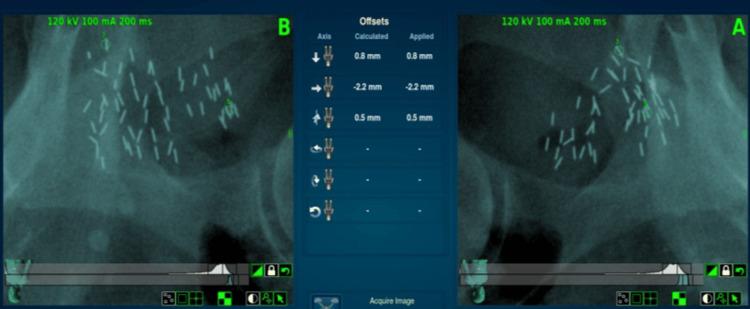

Locally recurrent prostate cancer after radiotherapy is a difficult clinical scenario. Focal therapy with stereotactic body radiation therapy (SBRT) is a promising treatment option. In this case report, we present the case of a male patient who underwent low dose rate (LDR) brachytherapy many years ago and experienced a prostate-specific membrane antigen positron emission tomography (PSMA PET) avid local recurrence of prostate cancer with rising prostate-specific antigen (PSA). He was able to undergo salvage CyberKnife (Accuray, Madison, WI) robotic radiosurgery without the need for additional fiducial marker placement by tracking previously implanted brachytherapy seeds. Treatment of 40 Gy in five fractions to the PET avid tumor gross tumor volume (GTV) and 35 Gy in five fractions to the planning target volume (PTV) was successfully delivered with minimal toxicity. The patient tolerated therapy well with excellent urinary and sexual functioning and declining PSA at the last follow-up.

放疗后局部复发性前列腺癌是一种棘手的临床情况。立体定向体部放射治疗(SBRT)聚焦治疗是一种有前景的治疗选择。在本病例报告中,我们介绍了一名男性患者的病例,该患者多年前接受了低剂量率(LDR)近距离放射治疗,现出现前列腺特异性膜抗原正电子发射断层扫描(PSMA PET)显示前列腺癌局部复发且前列腺特异性抗原(PSA)升高。通过追踪先前植入的近距离放射治疗种子,他能够接受挽救性射波刀(Accuray,麦迪逊,威斯康星州)机器人放射外科手术,而无需额外放置基准标记物。以最小的毒性成功地对PET显示的肿瘤大体肿瘤体积(GTV)分五次于每次8 Gy给予40 Gy的治疗,对计划靶体积(PTV)分五次于每次7 Gy给予35 Gy的治疗。患者对治疗耐受性良好,泌尿和性功能良好,在最后一次随访时PSA下降。